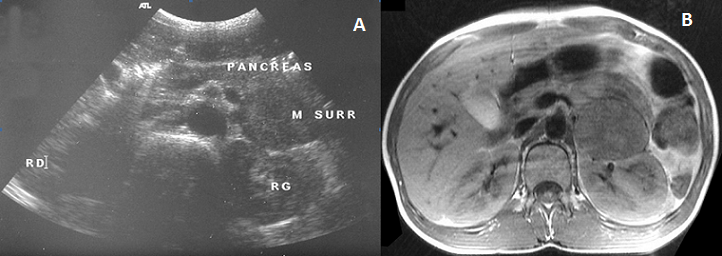

Le phéochromocytome est une tumeur rare chez l'enfant, ses manifestations cliniques résultent d'une excrétion croissante de catécholamines. L'hypertension artérielle est le signe révélateur principal. HMS, garçon âgé de 13 ans est hospitalisé pour hypertension artérielle sévère. Il se plaignait depuis plusieurs mois de céphalées, palpitations et d'accès de sueurs. L'examen physique a trouvé un enfant eutrophique, hypertendu (200/130 mm Hg) et tachycarde (135 pulsations par minute). L'examen cardiovasculaire était normal. L'électrocardiographe et l'échographie cardiaque était normaux. Il existait une rétinopathie hypertensive stade II au fond d'œil. La glycémie à jeun est à 6,5 mmol/litre; le taux des VMA à la limite supérieure de la normale (8mg/l). L'échographie abdominale a mis objectivée une masse hétérogène de 44 mm de grand axe en rapport avec la surrénale gauche. Au scanner, cette masse semble appendue à la queue du pancréas, donnée réfutée par l'échographie endoscopique (A). L'IRM abdominale a confirmé l'origine surrénalienne de la masse en montrant une formation ovalaire de 40×60 mm en hyposignal T 1 et hyper signal T 2, refoulant le rein gauche (B). Le patient fut opéré sous anesthésie générale après un équilibre tensionnel parfait. Le temps peropératoire a été marqué par la survenue d'un collapsus, suivi d'asystolie récupérée après 3 minutes de réanimation avec un état hémodynamique stable au cours et après l'intervention. Le phéochromocytome a été confirmé par l'étude histologique de la pièce opératoire. L'enfant âgé actuellement de 15 ans se porte bien avec des contrôles cliniques et échographiques satisfaisants.